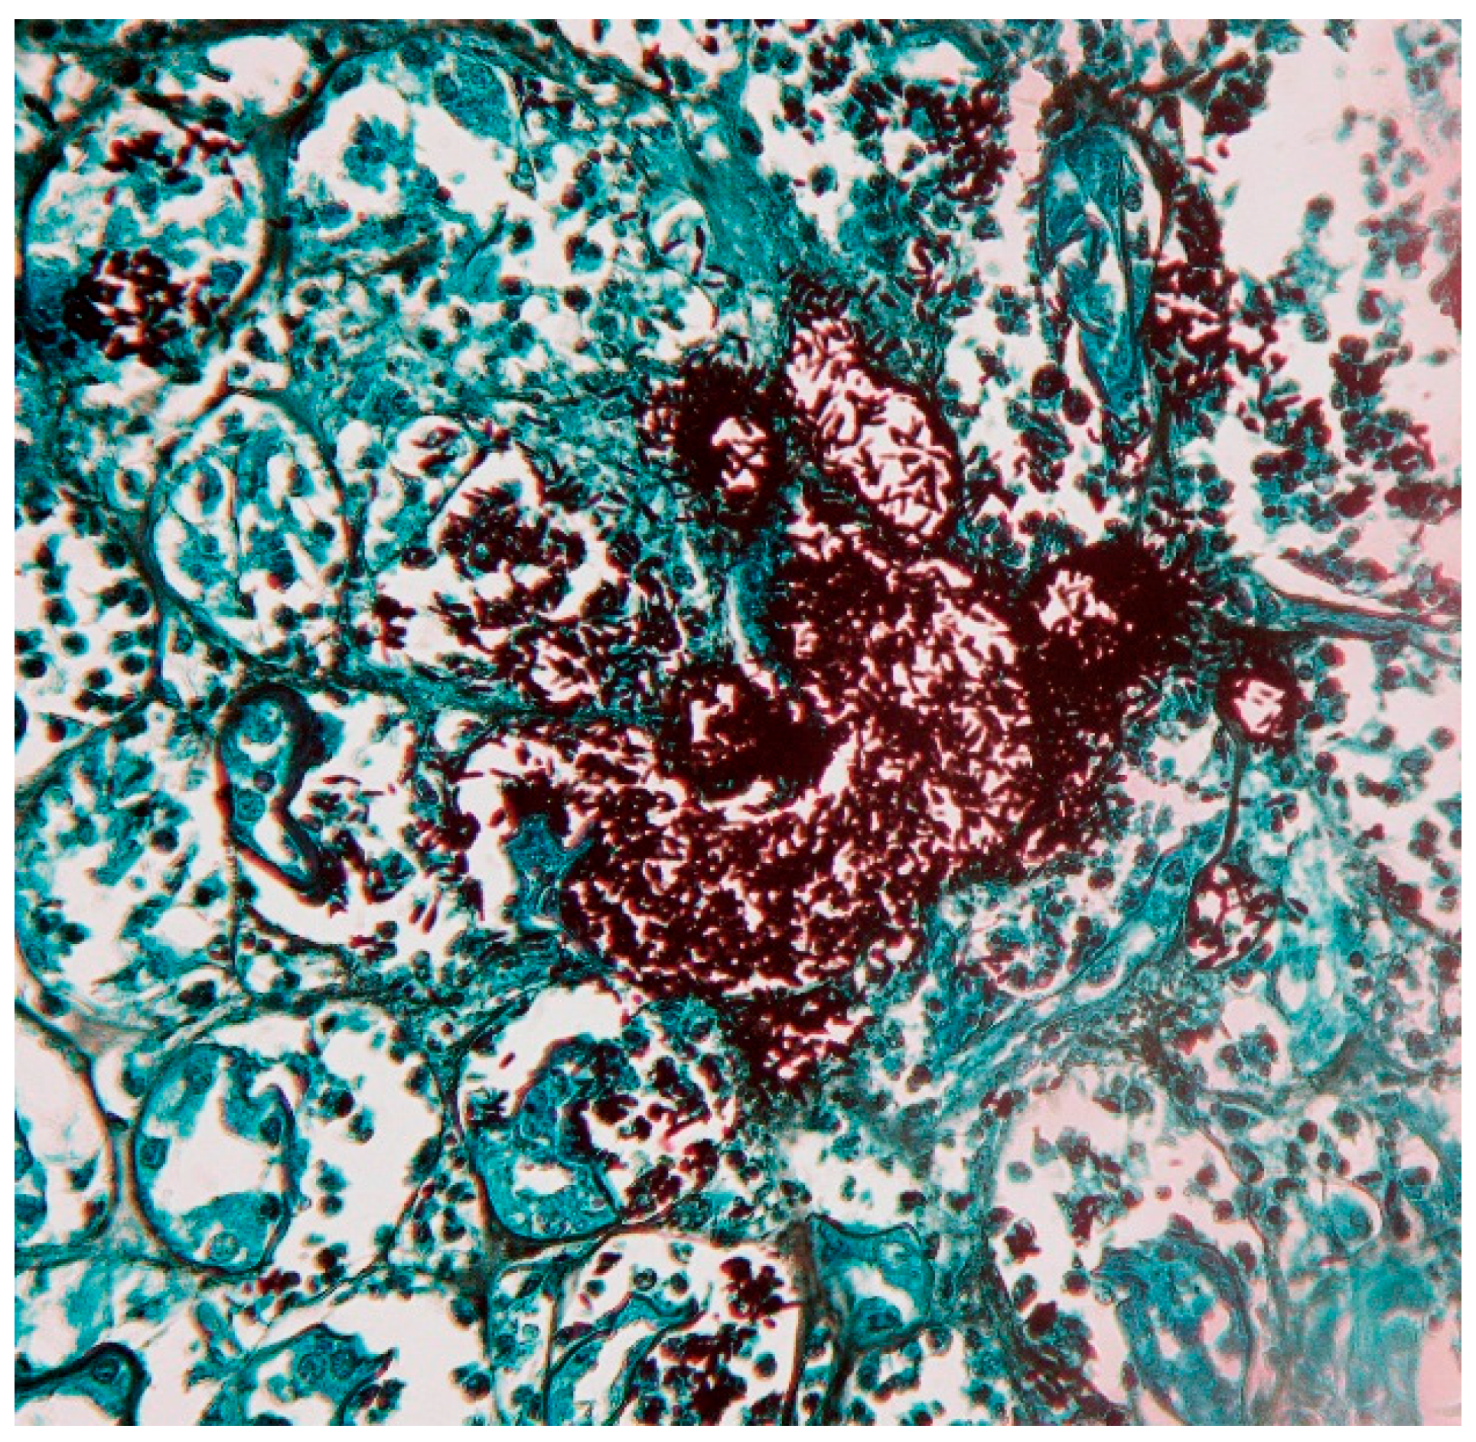

Direct examinations and staining are not useful for diagnosis of cutaneous-lymphatic and cutaneous-fixed sporotrichosis, since yeasts are observed only in a low percentage (5%–10%), whereas in cases of cutaneous-disseminated, disseminated and pulmonary sporotrichosis, Gram, Giemsa, Periodic Acid–Schiff (PAS) and Gomori-Grocott stains are useful for diagnosis as well as immunofluorescence techniques [3,4,11,70]. Yeast forms are usually round, oval or lengthened, described as “cigar-shaped” (Figure 2); in cases of immunocompromised patients, large clusters of yeast are observed, similar to feline sporotrichosis [8,29]. Differential diagnosis includes mainly histoplasmosis; in fungemia [3,4,35,36], yeasts are easily observed from blood imprints and no special staining is required [4,38,71,72].

Figure 2.

Biopsy of disseminated sporotrichosis. Renal biopsy with multiple clusters of lengthened yeast forms “cigar-shaped” (Grocott, 40×).